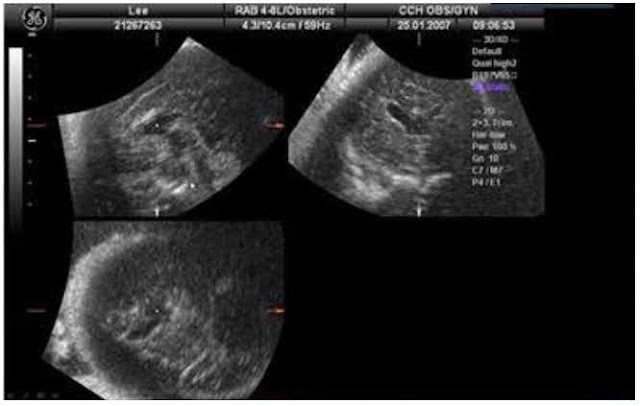

接下來彰化基督教醫院婦產科的謝聰哲醫師和大家分享了幾個後顱窩異常的經典案例。謝醫師開宗明義叮囑大家不能在妊娠十八週以前診斷DWM(Dandy-Walker malformation),原因是小腦蚓部在這個週數下本來就仍在發育。2006年Y. Zala發表在ISUOG的論文更提及當枕大池徑擴大的時候,有可能會造成小腦蚓部的旋轉,因此利用矢狀切面(sagittal view)觀察小腦蚓部的完整性是非常重要的!另外,在Joubert syndrome的個案中,常會把小腦半球誤以為是小腦蚓部,所以必須確認可清楚看到正常的fastigial point才能判定為小腦蚓部;也可以利用2019年K. K. Haratz發表在ISUOG的論文所提及的「fourth ventricle index」,正常的情況下,第四腦室的橫徑一定比前後徑來得大。值得注意的是,2002年G. Malinger發表在ISUOG的論文做了回溯性研究,發現第二孕期篩檢正常的胎兒,還是有16.7%是有中樞神經系統(central nervous system)的異常。

圖二、謝聰哲醫師提及可以利用3D超音波輔助診斷。